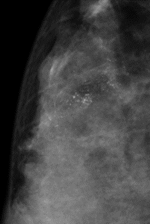

マンモグラフィ検査は、乳房を板で挟んでやや圧迫した状態でX線(乳房専用撮影)を行い、乳房内部の構造や石灰化、腫瘤(しこり)の有無を画像で確認する検査です。

乳房内に現れる異常陰影や微細な石灰化を探すのに非常に有効で、乳がんの早期発見に欠かせない検査の一つです。

さらに圧迫時間も以前より短くなり、被ばくも基準の半分以下で撮影可能です。乳がんの代表的な病変である腫瘤・石灰化をマンモグラフィにて観察することが出来ます。

上の図は石灰化の所見を示しています。